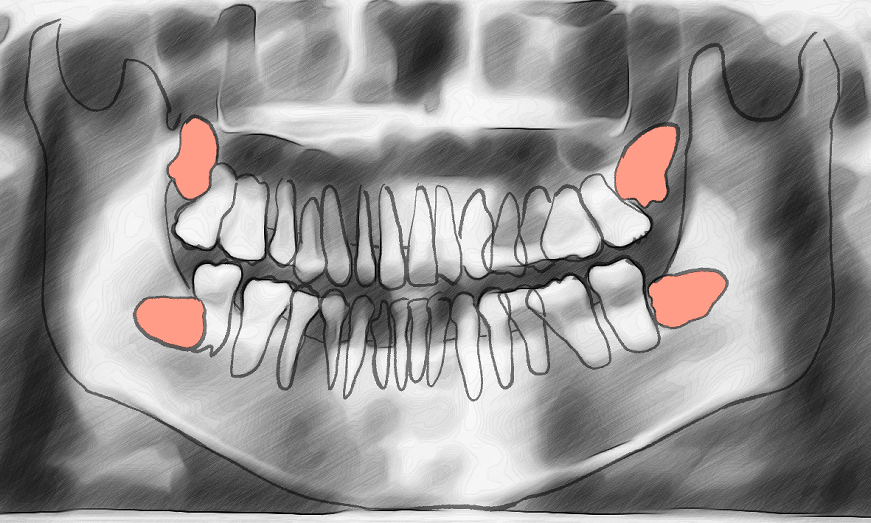

안뽑아도 된다는 의견 가지고 뭐라고 하는 사람들 많은데 실제로 요즘에는 잇몸 밖으로도 드러나지 않는 뼈 안쪽으로 매복된 완전매복사랑니는 안뽑는게 추세임

작성자가 그린 그림이 실제 엑스레이를 반영한다면 실제 잇몸라인은 여기서 붉은색 라인에 가까움 그러면 4개 사랑니가 모두 잇몸 안쪽에서 완전매복상태라 성인 기준으로 더 이상 성장가능성이 없다면 안뽑아도 됨 일부가 잇몸 밖으로 드러나는 경우에 맞닿은 이가 썪는거고, 밀린다는 얘기도 성장기에나 적용되는거라 작성자가 완전성인인 경우엔 특별한 사정이 없다면 뽑지 말라고 할걸 | 25.12.04 20:28 | | |